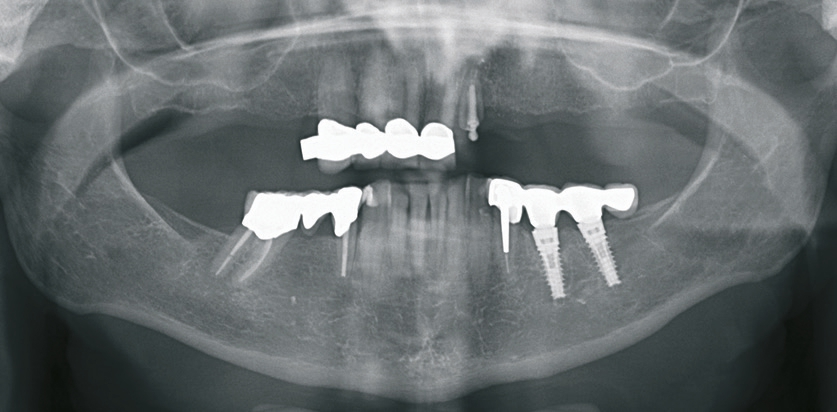

Die seinerzeit 68-jährige Patientin stellte sich im Jahr 2015 in der Klinik für Rekonstruktive Zahnmedizin und Myoarthropathien an den Universitätskliniken für Zahnmedizin in Basel vor, mit dem Wunsch nach einer langfristig stabilen Versorgung im Oberkiefer. Sie war im Oberkiefer mit einer bereits mehrfach angepassten alio loco hergestellten Teilprothese versorgt. Die medizinische Anamnese war unauffällig. Die Mundhygiene der Patientin war bereits zu dem Zeitpunkt auf einem guten Niveau und die parodontale Situation war abgesehen von lokalisiert leicht erhöhten Sondierungstiefen um den längsfrakturierten Zahn 22 sowie beim Implantat in regio 35 stabil. Neben den verblockten Kronen 13-12-11-21 wurde auch die gemischt zahn- und implantatgetragene Brücke 34-35i-36i-x aufgrund mangelhafter Passgenauigkeit als erneuerungsbedürftig eingestuft. Die definitive Neuversorgung im Unterkiefer sollte jedoch auf Wunsch der Patientin bis zum Abschluss der Versorgung im Oberkiefer aufgeschoben werden. Die über 20-jährige Brücke 34-x-36 konnte hingegen sowohl klinisch als auch radiologisch als suffizient eingestuft werden (Abb. 1 u. 2).

Nach Abschluss der Vorbehandlung erfolgte die Implantatplanung. Dazu wurde die neu angefertigte ideal ausgerichtete Drahtklammerprothese dubliert und das Duplikat als Röntgenschablone verwendet. Mithilfe der Planungssoftware NobelClinician ® (Nobel Biocare, Göteborg, Schweden) wurden möglichst weit distal und damit unmittelbar vor dem Sinus maxillaris zwei Implantate in regio 15 und 25 geplant (Abb. 6). Anschließend wurde die Röntgenschablone im Bereich der geplanten Implantatpositionen angepasst, sodass sie als Orientierungshilfe bei der Implantation verwendet werden konnte (Abb. 7). Die Implantationen erfolgten unter Lokalanästhesie in einer Sitzung. Es wurde ein geschlossenes Einheilverfahren gewählt. Zur postoperativen Kontrolle der Implantatpositionen wurde eine Orthopantomografie angefertigt (Abb. 8).